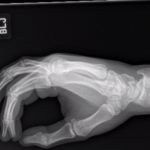

Significant findings:

A two-view radiograph of the right hand was obtained which revealed a dorsal dislocation of the distal fourth and fifth metacarpals (see red and blue outline, respectively) with a concomitant fracture of the distal fifth metacarpal (see yellow line) and avulsion fracture of the lateral aspect of the hamate (see green line). After reduction the fourth and fifth metacarpal dislocations are resolved; however, the distal fifth metacarpal fracture (yellow line) and avulsion fracture of the lateral aspect of the hamate (green line) are still visible.